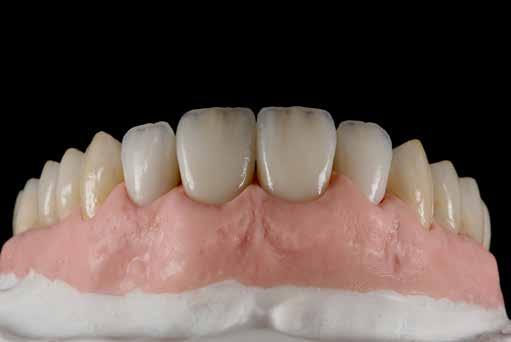

A front régióban alkalmazott minimál invazív multidiszciplináris megközelítés eredményeként jelentős mértékben tudtuk javítani a páciens esztétikai megjelenését. A beavatkozások során japán washi papír felhasználásával történő belső fogfehérítést, valamint háromdimenziós nyomtatással készült sebészeti sablon által vezetett ínyplasztikát végeztünk, majd az esztétikai zónában lévő fogakat – köztük egy elszíneződött nagymetsző fogat – ultravékony földpátkerámia héjakkal láttuk el.

A páciens elsősorban a mosolyának megjelenésén szeretett volna javítani. Egy előzetes állapotfelmérést követően az elszíneződött fog belső fehérítését, ínyplasztikát, valamint a felső front- és első kisőrlőfogak esztétikai célú helyreállítását javasoltuk. A belső fogfehérítés során nátrium-perborát és 30%-os hidrogén-peroxid keverékével átitatott washi papírt alkalmaztunk. Az anyag pulpakamrába történő helyezését követően az üreget üvegionomer cementtel zártuk. A fogfehérítés befejezését követően 3D nyomtatott sebészi sablont készítettünk, majd a felső front régióban megfigyelhető lágyrészek lefutását ezen sablon segítségével korrigáltuk. A sebészi beavatkozást követően 6 hónappal ultravékony földpátkerámia héjakat készítettünk.

ás, majd #0-ás retrakciós fonalakat (Ultrapak, Ultradent Products Inc, South Jordan, Utah, Egyesült Államok) helyeztünk. A végső precíziós lenyomatot polivinil-sziloxán lenyomatanyaggal (Virtual 380, Ivoclar Vivadent AG, Schaan, Liechtenstein) vettük. A fogtechnikai fázisban ultravékony (0,5 mm-nél vékonyabb) földpátkerámia héjak elkészítését kértük (Super Porcelain Ex-3, Kuraray Noritake Dental, Tokió, Japán), (7. ábra). A kerámia héjak készre vitelét követően a próba során a héjakat a helyükre illesztettük a széli zárást, az így kialakított fogformák ellenőrzése céljából. A páciens elégedett volt az így kapott látvánnyal. A végleges ragasztás kofferdám izolálásban történt. A preparált fogak felületét először 37%-os foszforsavval (Total Etch, Ivoclar Vivadent) 15 másodpercen keresztül kondicionáltuk, majd vízzel leöblítettük (8. ábra). A kondicionált zománcfelszíneket Adhese Universal (Ivoclar Vivadent) adhezívvel kezeltük. A kerámiahéjak homorú felszíneit 5%-os folysavval (IPS Ceramic Etching Gel, Ivoclar Vivadent) 20 másodpercen át kondicionáltuk, majd a felszíneket Monobond Plus primerrel (Ivoclar Vivadent) vontuk be (7. és 8. ábrák). A héjakat fényre kötő rezinalapú ragasztócement (Variolink Esthetic LC, Ivoclar Vivadent) applikálását követően a helyükre illesztettük. A kifolyó cementfelesleg eltávolítását követően minden felszínt (labiális, palatinális, meziális és distális) LED-es polimerizációs lámpával (VALO Cordless, Ultradent) 40 másodpercen keresztül megvilágítottuk.

A páciens elégedett volt a végleges restaurátumok színével, formájával és méretével. A kezelés végeredménye kielégítette az esztétikai elvárásait (9. ábra). A frissen átadott restaurátumok épségének megőrzése érdekében a páciens számára éjszakai fogvédősínt készítettünk. A páciensünk a négyéves kontrollvizsgálat során is nagyon elégedett volt a kezelés eredményével. A korábban meglévő fekete háromszögek eltűnésének különösképpen örült (9. és 10. ábrák)

Jelen esettanulmányban három meglévő technika kombinálását és továbbfejlesztését mutattuk be: washi papír használatával történő belső fogfehérítést, nyomtatott sebészi sablon által vezetett ínyplasztikát, és a fogakra ultravékony földpátkerámia héjakkal történő ellátását. E bonyolult eset kezelése során – minimálinvazív megközelítés mellett – kiemelkedő esztétikai eredményt sikerült elérni.

Az alapos tervezést követően végzett restauratív beavatkozások során sikeresen kombináltuk a washi papírral végzett belső fogfehérítést, a 3D nyomtatott sebészeti sablonnal és elektrokauterrel végzett ínyplasztikát, továbbá az ultravékony földpátkerámia héjakkal történő ellátást. A kezelési terv követésével el lehetett érni a kívánt esztétikai eredményeket, amelyek már 4 éve stabilnak bizonyultak.